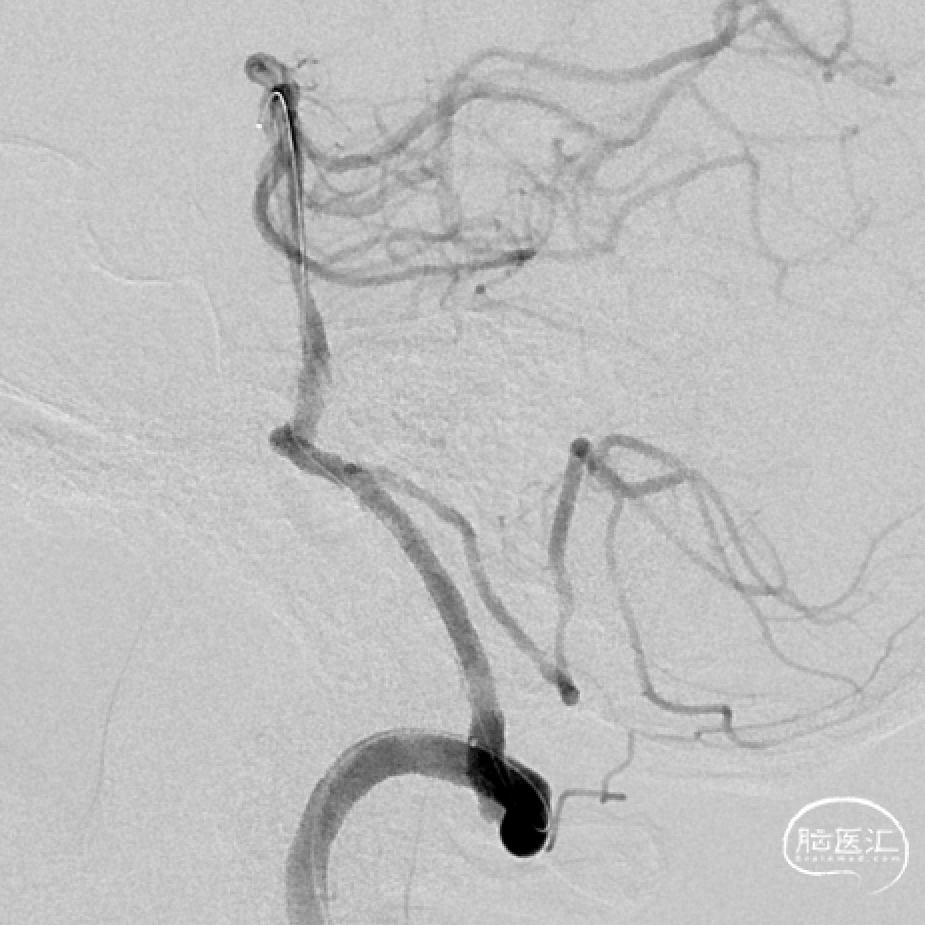

DSA示:右侧椎动脉V4段重度狭窄(85%以上)。

用赛诺神畅 2.75-15mm Neuro RX®颅内球囊扩张导管经交换导丝导引下至椎动脉狭窄处,3atm扩张90s。

再次用赛诺神畅 2.75-15mm Neuro RX®颅内球囊扩张导管4atm大气压扩张120s。

手推造影示:远端血流改善明显,椎动脉程度减轻至10%。赛诺神畅 3.5-20mm COMETIU™自膨式颅内药物涂层支架系统经交换导丝输送至狭窄远端,由远及近缓慢释放支架,支架完全覆盖狭窄段,造影示:椎动脉狭窄完全纠正,远端血流良好。

10分钟后复查造影提示椎动脉狭窄完全纠正,远端血流良好。试验器械成功植入目标病变血管部位,输送系统成功,系统成功回撤,器操作成功。

术后6个月随访:

2023-08-17复查脑血管造影示:右侧椎动脉V4段狭窄支架术后,支架在位,形态良好,未见再狭窄。

术后18个月随访:

2024-08-14复查脑血管造影示:右侧椎动脉支架术后,管腔内尚通畅。

治疗后随访影像对比: